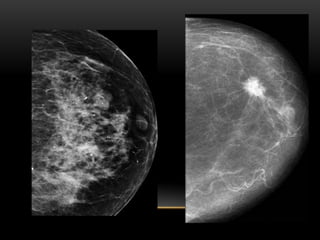

PATRÓN DE TEJIDO

MAMARIO

PATRÓN DEL TEJIDO GLANDULAR

MAMOGRÁFICO (COMPOSICIÓN

TISULAR MAMARIA):

1. Fibroadiposo escasa cantidad(- 25 %

glándula)

2. Fibroglandular moderada cantidad (25-50%

3. Densidad heterogénea (51-75% glándula)

4. Extremadamente denso(+ 75% glándula)

FIBROGLANDULAR ESCASA CANTIDAD

FIBROGLANDULAR MODERADA CANTIDAD

HETEROGENEAMENTE DENSO

EXTREMADAMENTE DENSO

ECOGRÁFICO:

1. Ecoestructura homogénea grasa

2. Ecoestructura homogénea

fibroglandular

3. Ecoestructura heterogénea